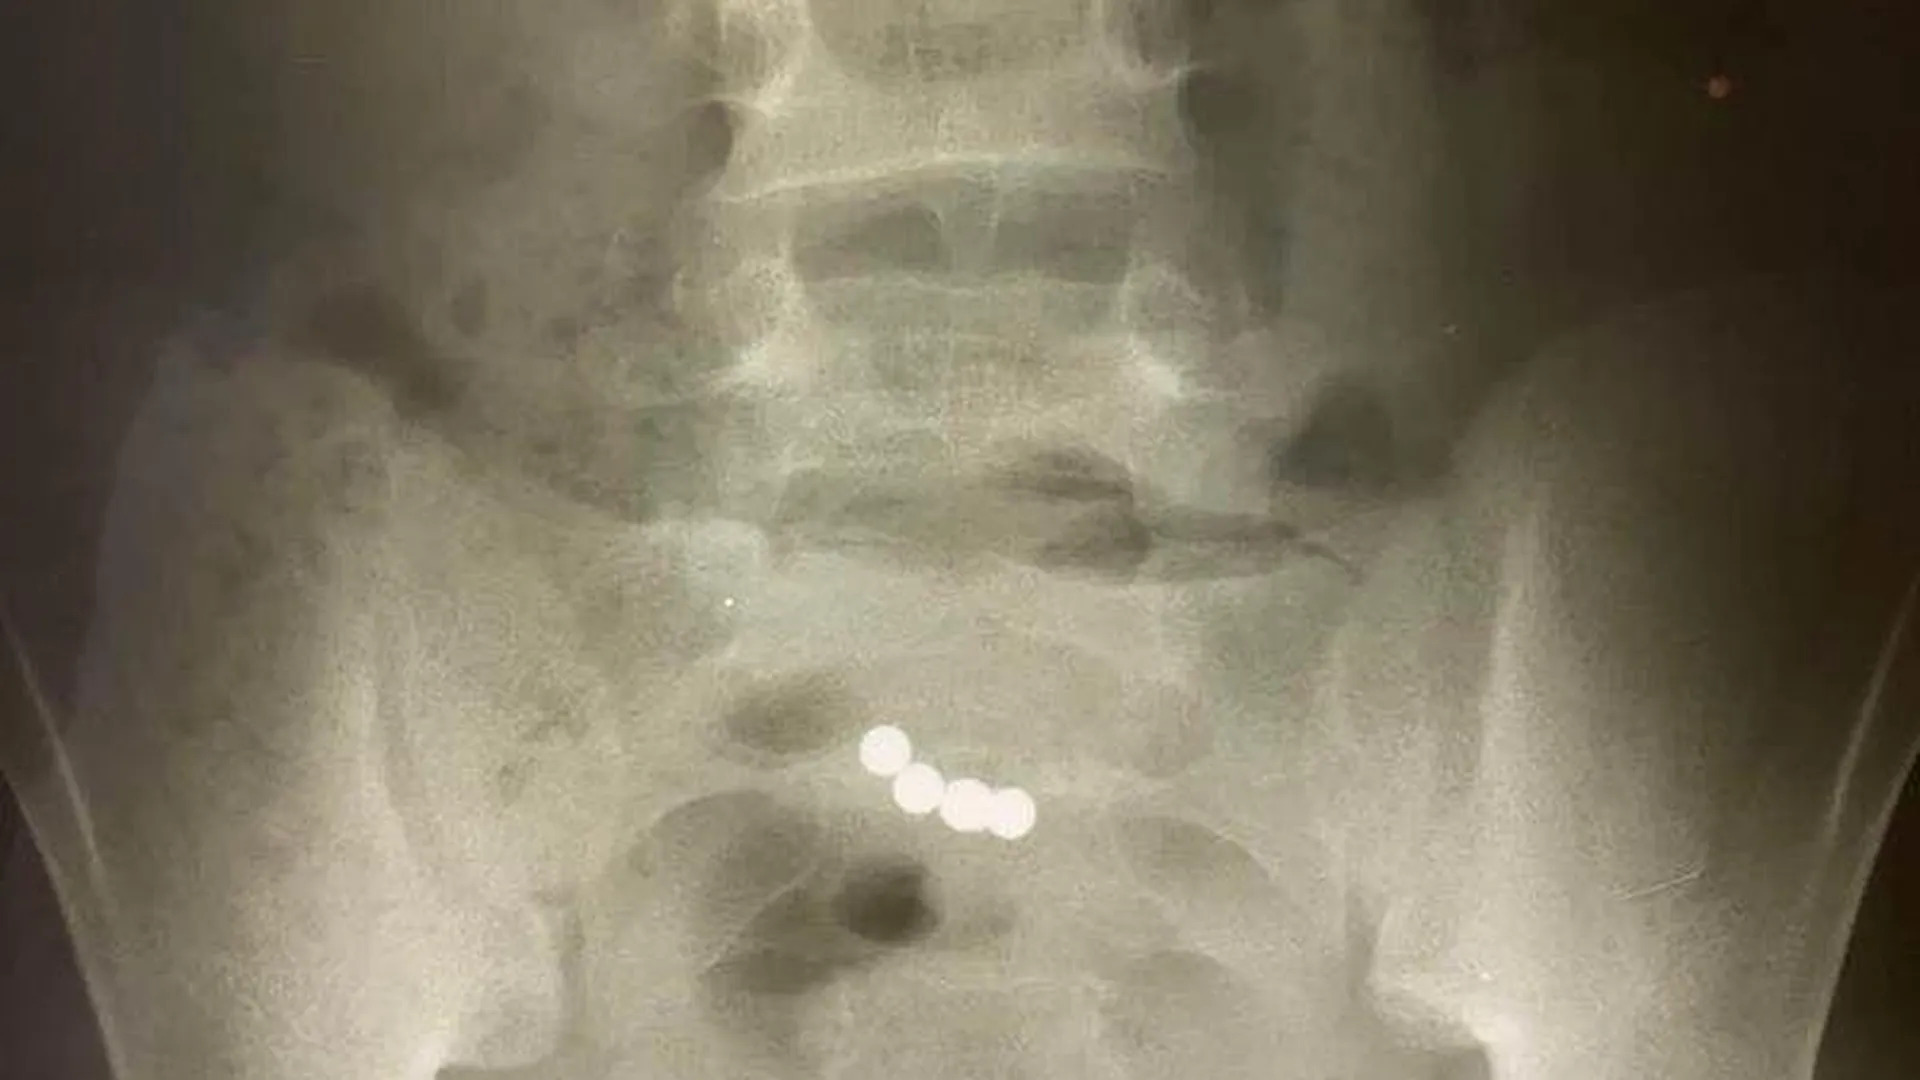

Проглотил болтик

Проглотил болтик 106 фотографий